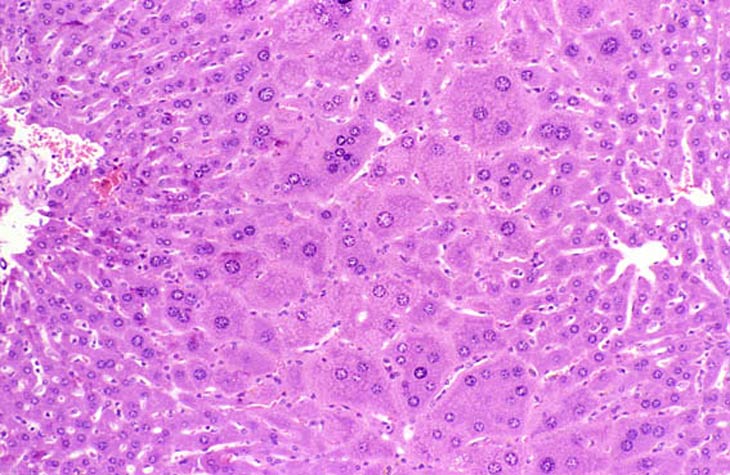

Extreme polyploidy consisting of cytomegalic hepatocytes with very large nuclei as well as cytomegalic hepatocytes with several diploid nuclei is seen in these images from a mouse treated with chlordane for 18 months.